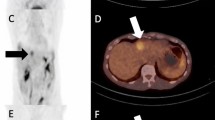

Sarcoid-like reaction is best known with ipilimumab, often presenting with mediastinal lymphadenopathy, pulmonary nodules, and splenic involvement (Fig. 12.6) [14]. It may also involve other nodal stations.

Sarcoid-like reaction on ipilimumab. FDG-PET/CT performed 3 months after the first dose of ipilimumab showed new mediastinal lymphadenopathy (short thin arrow), lung nodules (short thick arrow), and splenic uptake (long thin arrow). The report raised a possibility of metastatic disease; however, the findings resolved on the follow-up FDG-PET/CT at 6 months